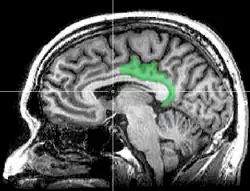

Posterior cingulate cortex

Sagittal MRI slice with highlighting indicating location of the posterior cingulate